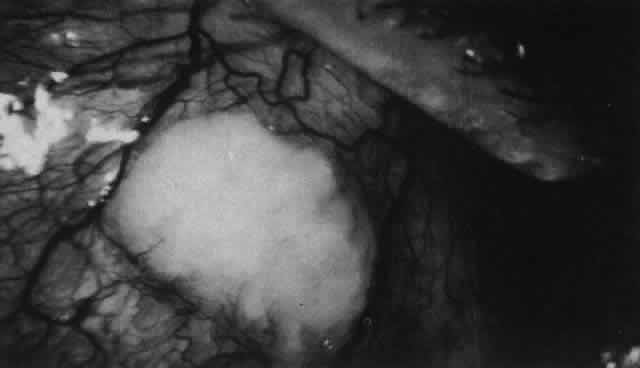

Posterior Scleritis

Because the posterior sclera is invisible, the diagnosis of posterior scleritis is made only if the anterior sclera is also involved or some other sign or symptom leads one to suspect it. Posterior scleritis is much more common than previously suspected, as recent clinical and pathologic studies have shown.19,28,29 There are two distinct forms of posterior scleritis. The first is usually associated with an anterior scleritis. This granulomatous disorder, like its anterior counterpart, can be diffuse, nodular, or necrotizing in character and is associated with the connective tissue diseases. The second form occurs in young patients of all races who are 9 to 40 years of age. It is always diffuse in character but is not associated with any systemic disorder. Both forms may cause uveitis if the inflammation affects the ciliary body, and in both forms the patient may develop exudative retinal detachments, choroidal folds, and swelling of the disc (Figs. 51 and 52). The granulomatous type may also involve the structures outside the globe, causing proptosis (Fig. 53), limitation of ocular muscle movement, and, uniquely, retraction of the lower lid on attempted elevation of the eye (Fig. 54). Diagnosis is with B-scan ultrasonography.

Fig. 51. Swelling of the optic nerve head and hemorrhage near the disc in a patient with posterior scleritis. The poor quality of the photograph is partly due to vitreous haze that accompanied the inflammation.

Fig. 52. Fundus appearance after resolution of exudative detachment in patient with severe posterior scleritis. Macula was affected and vision much impaired. (Watson PG: Management of scleritis. In: Recent Advances in Ophthalmology, Vol 5. London, Churchill-Livingstone, 1975)